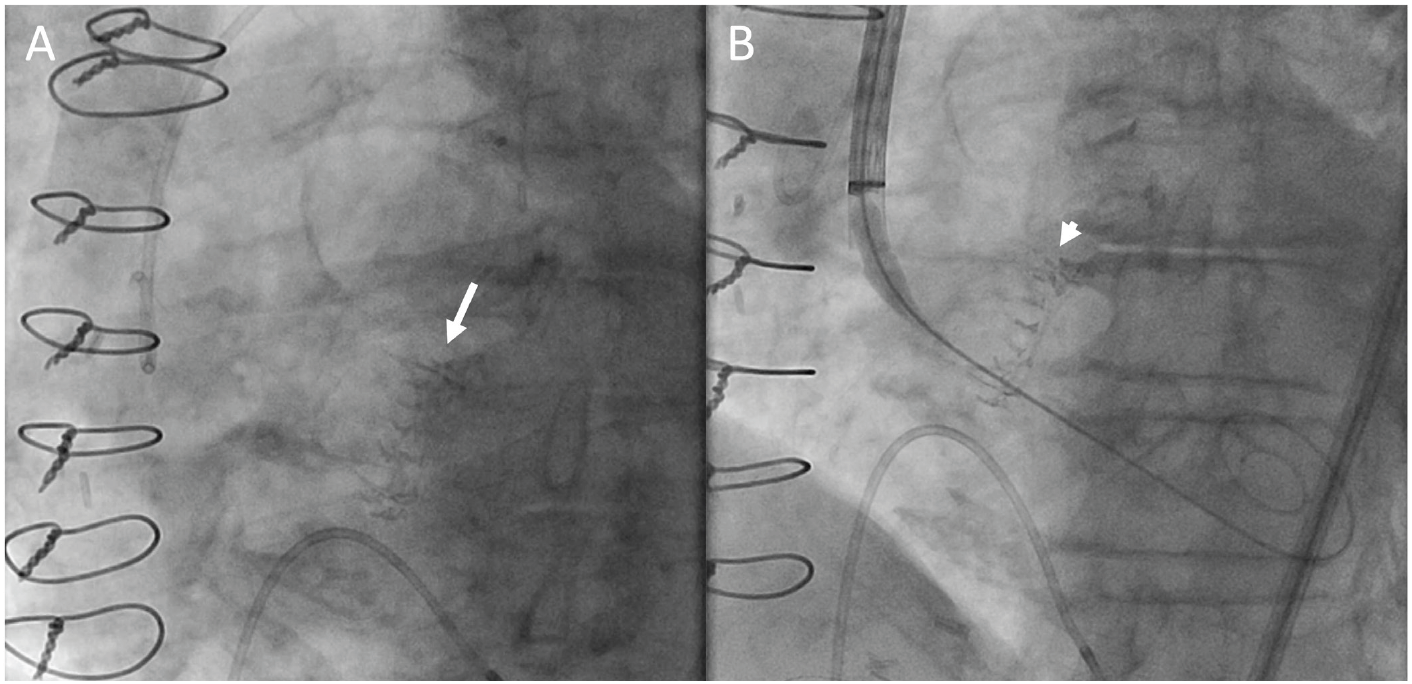

During the TAVR procedure, coplanar angle estimated from preoperative CT scan was easily adjusted referencing the line of Cor-Knot in her aortic annulus without administrating contrast although poor radiodensity from the Trifecta valve. In the coplanar view, the TAVR valve depth was well appreciated in reference to the Cor-Knot line and the TAVR valve was deployed under controlled pacing without contrast use (Figure 1 and Figure 2). We achieved mean aortic pressure gradient of 9 mm Hg without perivalvular leakage or conduction abnormalities. She was discharged to home the next day without renal injury.